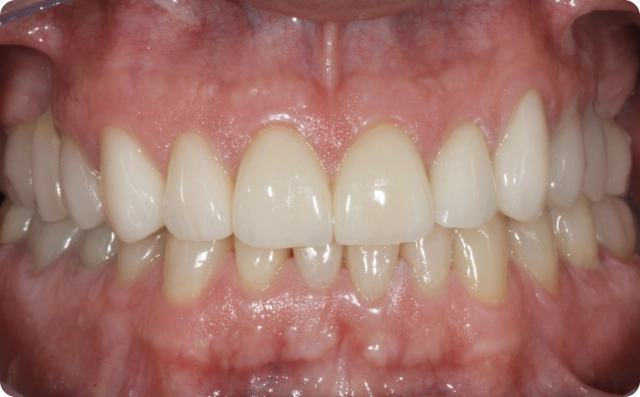

Antes

Depois

Foram confeccionadas facetas cerâmicas de dentes caninos a caninos superiores e inferiores, ponte fixa na região superior direita e coroas unitárias em dissilicato de lítio nos pré molares e molares.